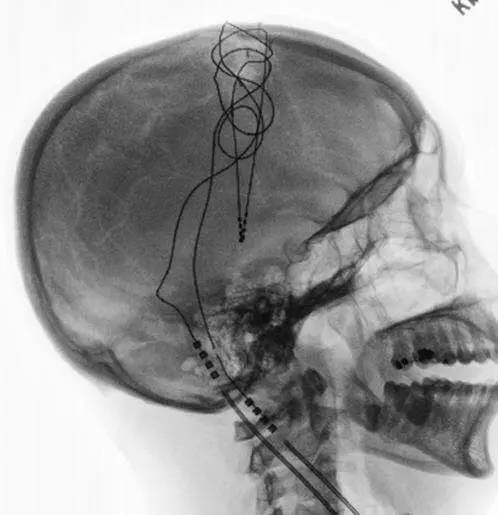

原發性巴⾦森⽒病患者治療⼀段時間之後,症 狀越來越嚴重,且左旋多巴胺的作⽤時間也變短,因⽽患者接受⼿術治療。從X光影像判斷患者是進⾏何種⼿術?

本題考核原發性巴金森氏病(idiopathic Parkinson's disease)進階手術治療的選擇,並透過 X 光影像判斷手術種類。重點在於辨識深層腦部刺激器(deep brain stimulator, DBS)的 X 光影像特徵,以及理解 DBS 適應症與手術機制。

圖片為頭顱側位 X 光片(lateral skull X-ray),可見以下特徵:

電極導線(electrode lead):一條細長、不透 X 光(radiopaque)的電極線,從顱頂部經由顱骨鑽孔(burr hole)進入顱內,延伸至腦深部目標核團(推測為視丘下核,subthalamic nucleus, STN,或蒼白球內側,globus pallidus internus, GPi)。

皮下盤繞的多餘導線(subcutaneous coiled excess lead):電極線在頂部顱骨外側有一大圈顯著的螺旋狀盤繞,這是 DBS 手術的標誌性影像特徵——外科醫師習慣將多餘長度的延長線盤繞於頭皮下或耳後,以便日後調整或更換。

延長線走向:電極線從頭皮盤繞處向下延伸,沿頸部走行,最終連接至胸前皮下的植入式脈衝發生器(implantable pulse generator, IPG)(此片未顯示胸部,但走向